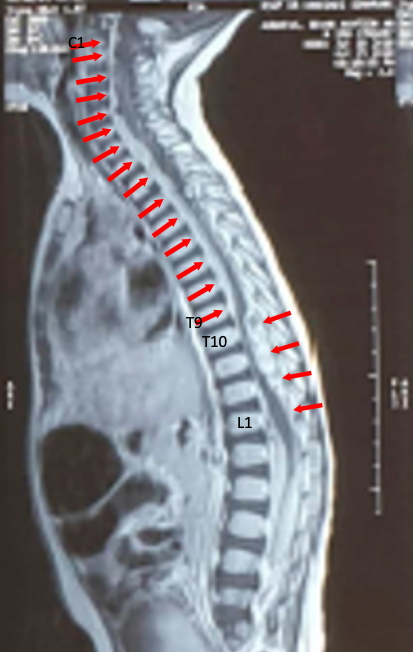

Case Presentation: A 15 month-old boy, with chief complain of difficulty in moving his leg and pain when walking, physical examination revealed a lower motor neuron lesion, laboratory showed a low factor VIII at 0.4% level, Magnetic Resonance Imaging (MRI) showed anterior and posterior displacement of the spinal cord due to the presence of the subacute subdural hematoma extending from 1st cervical to 1st lumbar spine. He assessed with inferior paraparesis caused by subacute spinal subdural hematoma due to hemophilia A. The patient’s condition was improved after received replacement therapy of factor VIII and proper laminectomy neurosurgery.

Figure 1. MRI of whole spine sagittal T1-weighted image and T2-weighted image revealed a subacute subdural hematoma extending from C1 to T9 on anterior aspect, then T10 to L1 on posterior aspect.